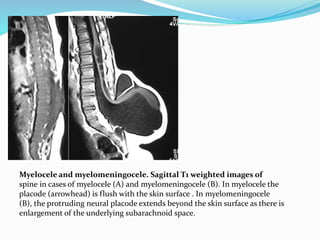

Myelocele and myelomeningocele. Sagittal T1 weighted images of

spine in cases of myelocele (A) and myelomeningocele (B). In myelocele the

placode (arrowhead) is flush with the skin surface . In myelomeningocele

(B), the protruding neural placode extends beyond the skin surface as there is

enlargement of the underlying subarachnoid space.

 In MMC, the protruding neural placode extends

beyond the skin surface as there is enlargement of the

adjacent subarachnoid space . This help to distinguish

MMC from the far rarer myelocele, where

the placode is flush with the skin surface